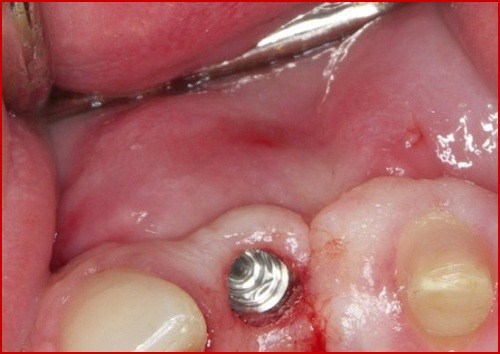

2.3 Tiêu xương hàm tại cổ trụ implant:

Biến chứng tiêu xương tại cổ trụ implant sẽ khiến phần thân trụ bị lộ ra khỏi nướu, làm mất thẩm mỹ. Nếu như không được xử lý kịp thời thì tình trạng này sẽ tiến triển nặng hơn, thân trụ sẽ bị lung lay gây ra các tình trạng về viêm lợi, hôi miệng và ảnh hưởng tới các răng bên cạnh.